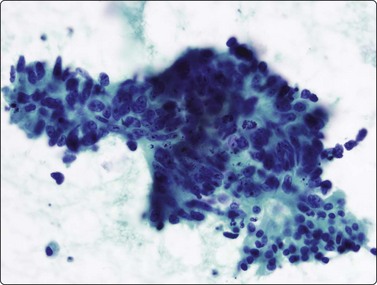

image image image

Fig. 8.28 High-grade neuroendocrine carcinoma; small cell carcinoma

(A, B) Smears showing ‘intermediate’ morphology. Loose aggregates of fragile cells with traumatization artifact and nuclear molding but some background cytoplasm (A, Pap, MP; B, H&E, HP). (C) Tissue section of resected peripheral stage 1 small cell carcinoma (H&E, HP).

image image image image image

Fig. 8.29 High-grade neuroendocrine carcinoma

Variable morphology including small cell and large cell patterns. (A) Low-power smear appearances of small cell carcinoma; (B) Higher-power examination shows some large cells with prominent nucleoli (A, H&E, LP; B, H&E, MP). (C,D) Tissue sections of resected peripheral stage 1 tumor showing areas of geographic necrosis and a predominance of large cells with prominent nucleoli (C, tissue section, H&E, LP, Inset, HP; D, tissue section, H&E, HP). (E) Positive immunostaining for chromogranin in resected specimen (E, tissue section, IPOX, HP).

Although ‘intermediate’ small cell carcinoma is no longer recognized as a separate category in international classifications, we find it a useful concept to highlight the occasional difficulty in distinguishing between small cell and poorly differentiated non-small cell carcinomas (Figs 8.28 and 8.29). There is overlap in nuclear size between small and large cell carcinomas and a tendency for inexperienced cytologists to include small cell carcinomas with larger than expected nuclei in the non-small cell category. In general, if the nuclear features of a problematical tumor are those of small cell carcinoma – that is, granular chromatin without prominent nucleoli – the neoplasm will usually fall into the small cell carcinoma group histologically, whereas vesicular nuclei with prominent nucleoli would generally be evidence of non-small cell tumor. However, large cell neuroendocrine carcinoma does provide special problems. Our experience is limited but is similar to Yang et al. who described various morphologic patterns in this family of tumors, including small cell-like and mixed small cell/large cell-like FNAC patterns.37 Cell size is therefore an important criterion and one to be critically evaluated. Tumors with nuclei larger than 2–3 times the diameter of a lymphocyte may be classified as LCNEC histologically, even if nuclear chromatin pattern and other cytological features are similar to those of small cell carcinoma (Fig. 8.29). Our approach is therefore to first come to a diagnosis of ‘high-grade neuroendocrine carcinoma’ and then to critically examine cell size and morphology to determine the best category – ‘small’ or ‘large’. We do, however, agree with the idea propounded by Marchevsky et al.89 that the distinction between the two categories may be somewhat artificial in view of the overlap in cell size between the two groups. This is an area which requires close cooperation with oncologists and an acceptance of the limitations of cytological diagnosis. It may be necessary to base management on clinical and staging findings in conjunction with inconclusive cytological tumor typing in some cases.